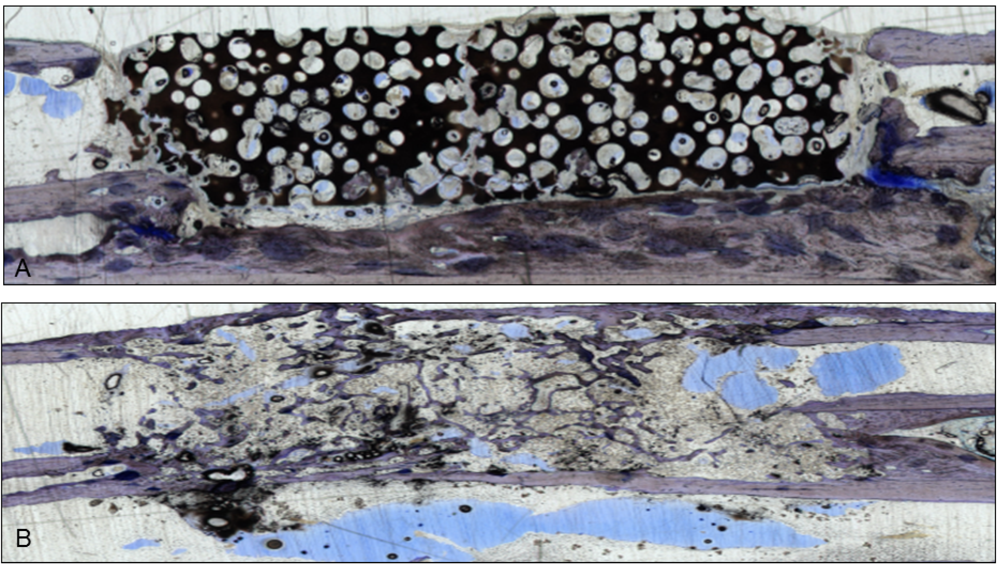

Figure 1.

Two sections stained with giemsa and toluidine-blue show the integration of the scaffolds in the bone gap. They were used to verify the µ-CT scans. (A) This section represents an example of CDHA without VEGF. The scaffold is still visible and barely degenerated, but bone grew into the lacunae;(B) After administration of VEGF-transfected BMSCs, almost the whole CDHA-scaffold had degraded and new bone filled the gap. Endothelial cells were stained with a monoclonal mouse anti-human CD31 antibody (Clone: JC70A Dako Cytomation Glastrup, Denmark; dilution 1:20) according to the manufacturer’s instructions [10,11]. All sections were examined with a light microscope by two independent observers.